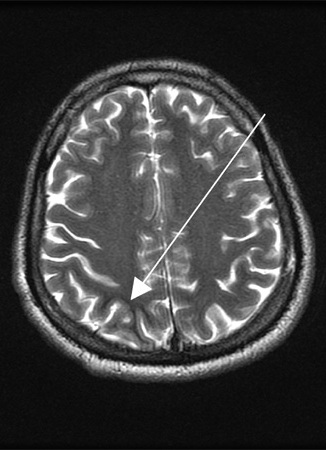

MRI brain

Test

Required if neurological symptoms.

Result

space-occupying lesion(s)